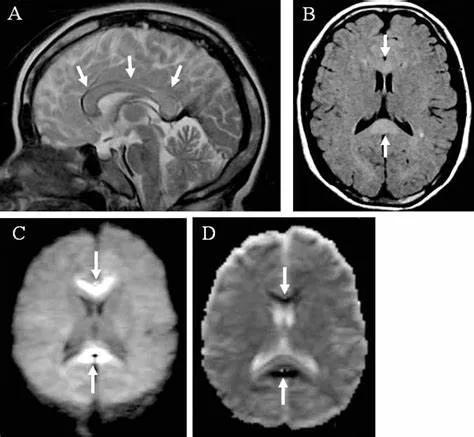

原发性胼胝体变性急性期:T2WI矢状位(A)清晰观察到弥漫胼胝体病变,FLAIR呈高信号(B),DWI呈高信号(C),ADC图呈低信号。